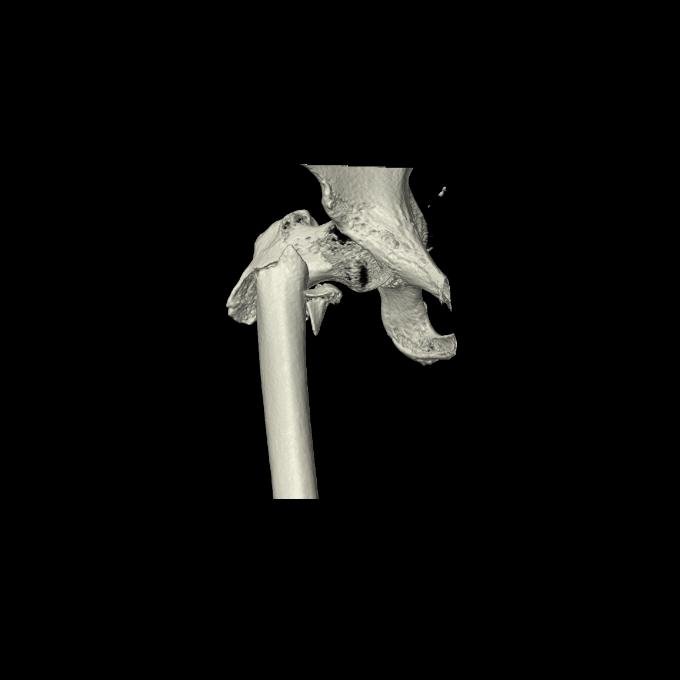

110286 2/17 股関節 2R 74歳女性 右人工骨頭

82084 1/14 1/20 股関節 2R 78歳男性 右人工骨頭

102811 1/13 股関節 2R 1/19 2R 80歳女性 右DHS

91569 3/25 両股正面とラウエン 70歳女性 人工骨頭+バンクーバー